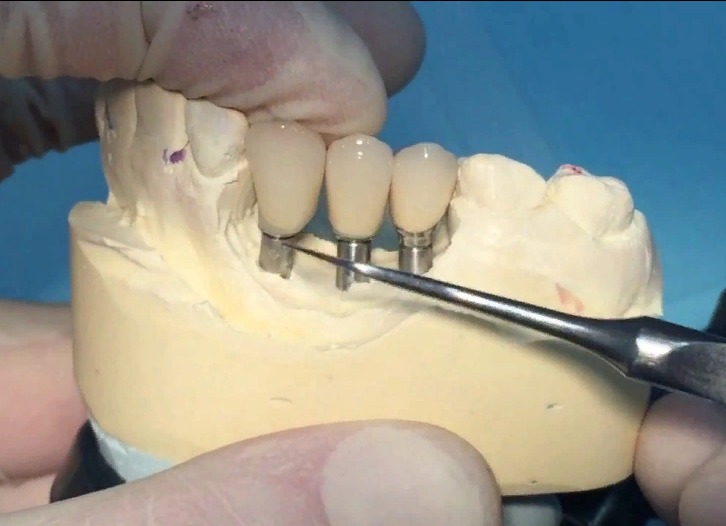

Современные коронки на зубные импланты: виды и фото-примеры